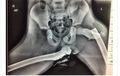

Knowledge

Foto X-ray Ini Buktikan Bahaya Meletakkan Kaki di Atas Dasbor Mobil